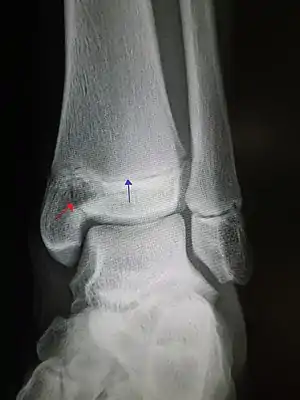

| An X-ray of the left ankle showing a Salter–Harris type III fracture of medial malleolus. Black arrow demonstrates fracture line while the white arrow marks the growth plate. | |

- Type III – A fracture through growth plate and epiphysis, sparing the metaphysis:[9] 8% incidence